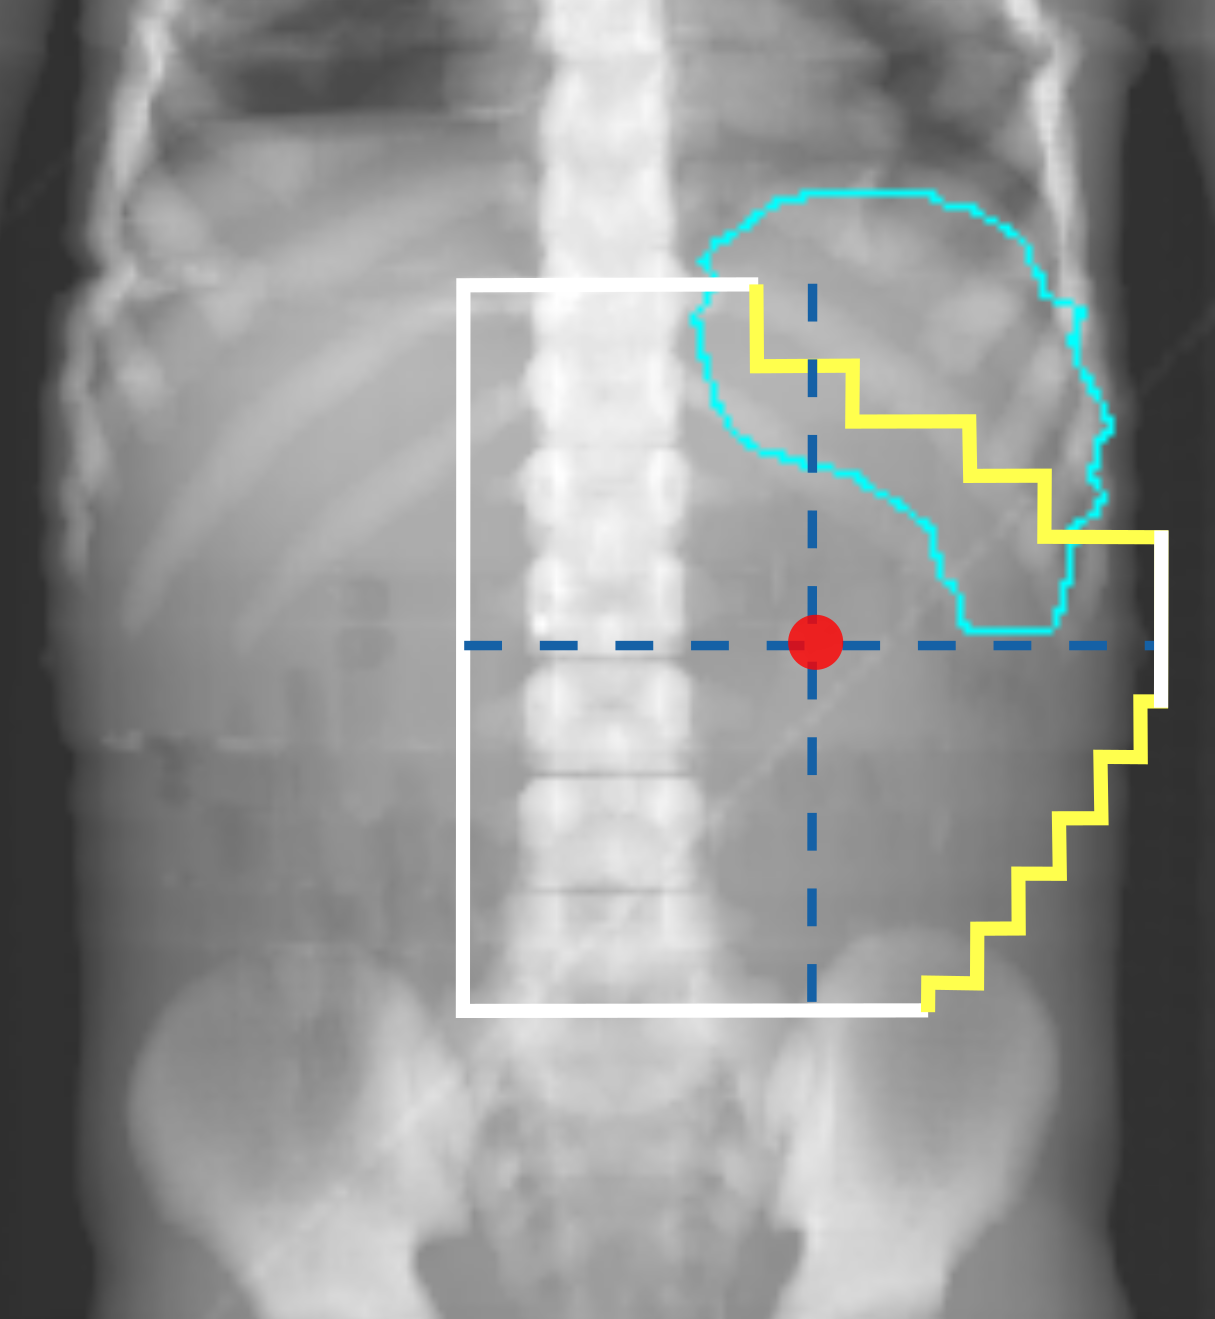

Figures 1(a) and 1(c) illustrate examples of actual historical plans on respective historical radiographs. As can be observed, a typical historical flank irradiation field is a rectangular area, with possible shielding blocks, that is located on the right or on the left flank. Irradiation is done by beams from anterior-posterior (AP) and posterior-anterior (PA) direction. Along right-left (RL), one field border is located at the edge of the patient’s body contour, while the other is located as to include the vertebral column (?). In some cases, blocks are placed to protect OARs from irradiation (Fig. 1(c)). In historical plans the isocenter is positioned in the center of the treatment field that is projected on the coronal plane (Fig. 1) and at the middle of the patient’s AP abdominal diameter.

For each plan generated, an additional version of that plan including one block was generated as well. A block was simulated as the area in the upper lateral corner enclosed by the border of the rectangular field and a line crossing two randomly sampled endpoints. The endpoints were sampled from two regions roughly covering the start and end points of rib 9 and rib 12 on the DRRs (regions indicated by the green boxes in Fig. 2). This way, a sampled block covered part of the liver (in right-sided plans) or part of the spleen (in left-sided plans). All plans consisted of two opposing and symmetrical beams in AP-PA directions irradiating one side of the abdominal flank. Figures 1(b) and 1(d) illustrate two examples of sampled artificial plans (without or with a block) on respective DRRs.

For some metrics and OARs, errors were relatively large for some of the clinical plans. This may be due to chance, because ten is a small number. For example, the large underestimation observed for the of the spleen for one clinical case (with and without block) is due to the ML-based approach wrongly predicting a value associated with a spleen that is located completely outside of the field. Another reason why errors were relatively large for the clinical plans is that the artificial plan generation method needs to be improved. Artificial plans were generated by sampling geometry properties uniformly within predefined boundaries on two reference DRRs. Uniform sampling might not be representative of the distribution clinical plans have. Moreover, we consulted a single radiation oncologist to define clinically acceptable boundaries to use in the sampling of artificial plans. Consulting multiple experts and allowing for a larger variation might better help covering the extent of variation that is present in historical plans (Sec. 2.2). For example, the isocenter locations of artificial left-sided plans were never sampled below the 1st lumbar vertebra (see Fig. 2) and approximately half of the values for the spleen in case of the artificial left-sided plans were close to the prescribed dose (14.4 Gy, see Fig. 5), which means that the spleen was often almost completely in-field in our artificially generated set of left-sided plans. When a block was applied, only a small part of the spleen was spared. However, in clinical practice, isocenter locations can be lower, and a larger part of the spleen might actually be outside the field (see Fig. 7). This might explain the relatively large errors observed in the two outlier cases in Figure 6 where the isocenter location of the clinical plans is lower than the sampled range. Ultimately, effort should be done to improve the sampling of artificial plans.